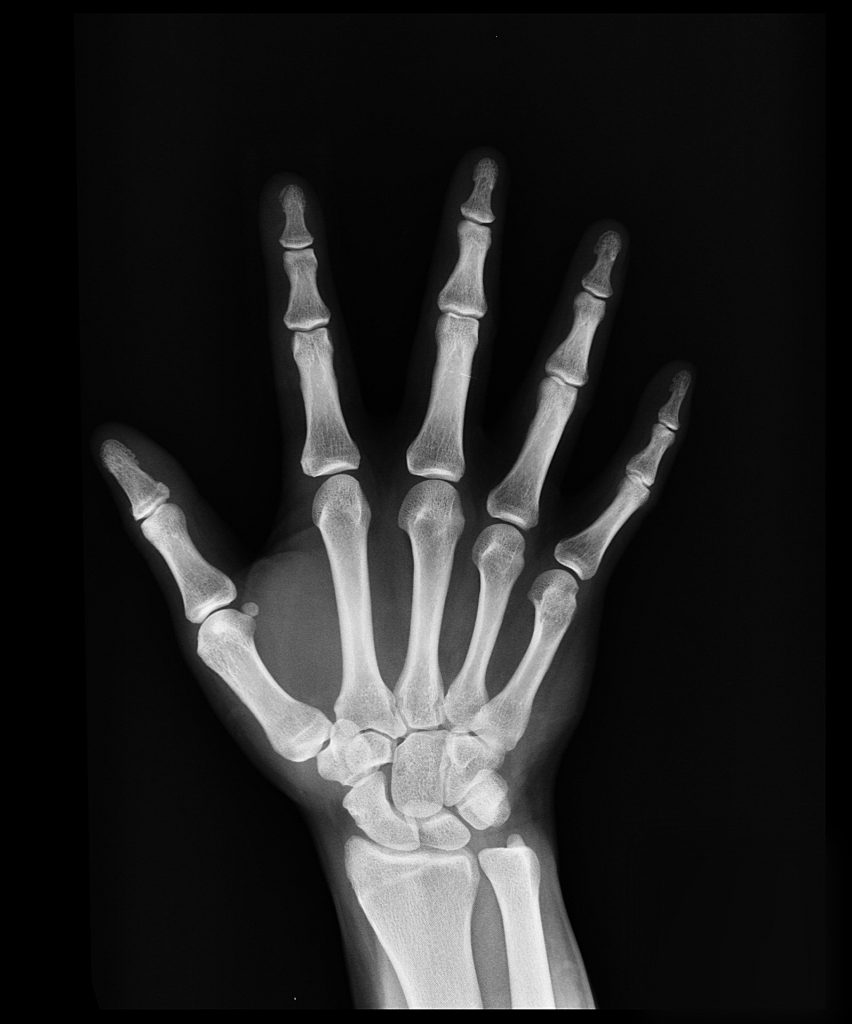

Xray image showing the left hand wrist in dorsal view. The carpal Hand And Wrist X Ray The radial and ulnar arteries, as well as their terminal branches, provide vascularity to the hand and wrist while the median, ulnar, and radial nerves are responsible for motor and. Although additional radiographs can be taken for specific indications. One of the commonest misses in trauma films of the hand. The hand series consists of posteroanterior, oblique, and lateral projections.. Hand And Wrist X Ray.

Xray of human Hand fingers top view. Xray of male hand and wrist. X Hand And Wrist X Ray Although additional radiographs can be taken for specific indications. This article provides a comprehensive approach to wrist radiographs, including techniques and common indications for imaging. This is the most commonly used test for wrist pain. The radial and ulnar arteries, as well as their terminal branches, provide vascularity to the hand and wrist while the median, ulnar, and radial nerves. Hand And Wrist X Ray.

Film xray hand radiograph show normal human anatomy of wrist, hand Hand And Wrist X Ray The radial and ulnar arteries, as well as their terminal branches, provide vascularity to the hand and wrist while the median, ulnar, and radial nerves are responsible for motor and. This article provides a comprehensive approach to wrist radiographs, including techniques and common indications for imaging. One of the commonest misses in trauma films of the hand. This is the. Hand And Wrist X Ray.